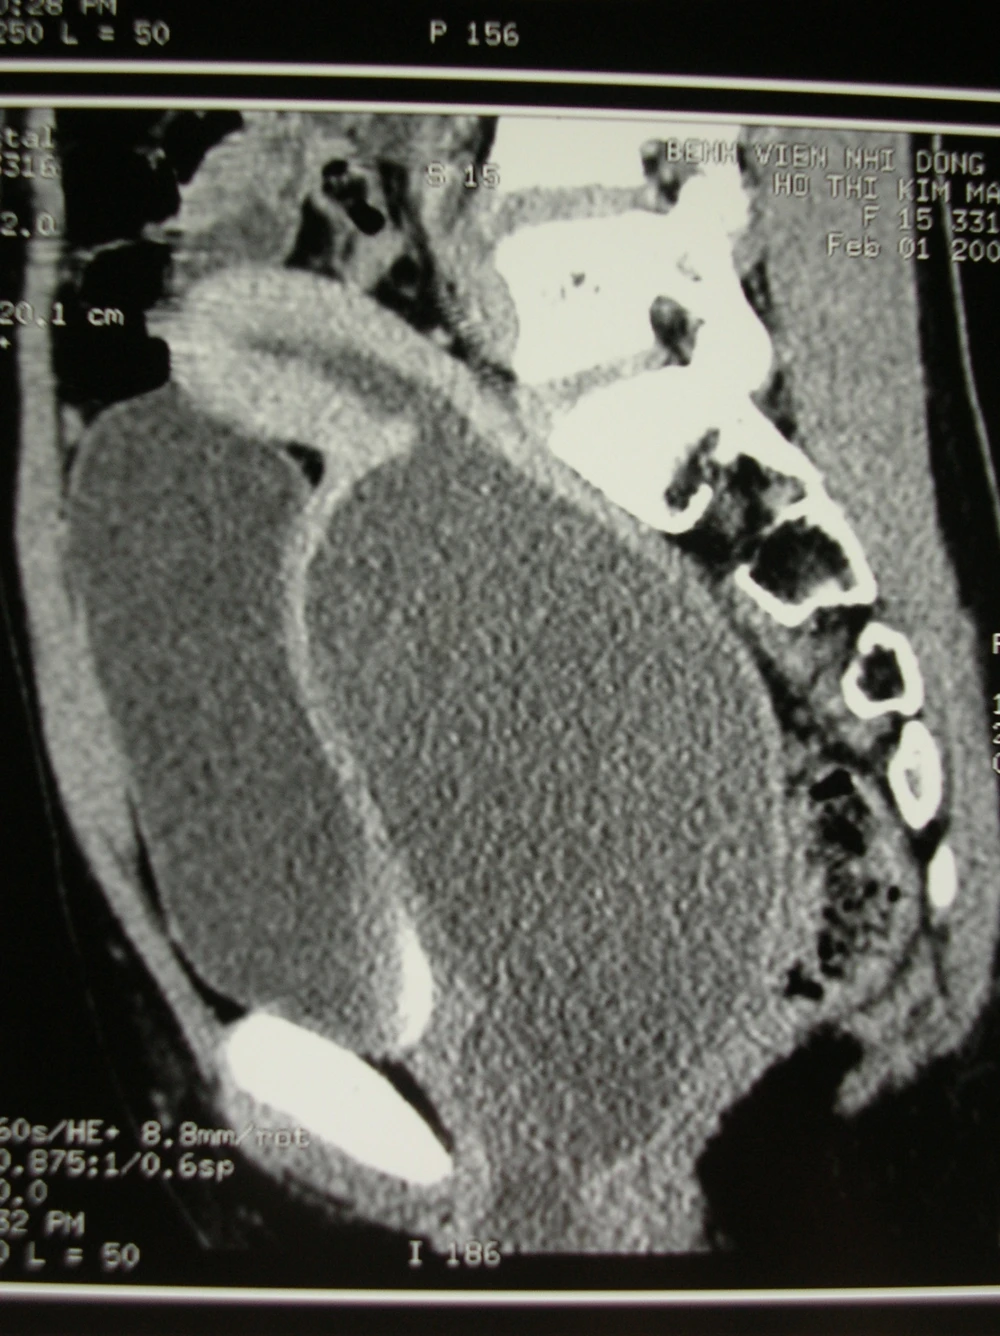

Hình chụp bệnh nhân H. Ảnh: BV Nhi đồng 2

Ba tháng trước, bé H. có những biểu hiện đau bụng theo chu kì hàng tháng. Mỗi đợt đau bụng như vậy kéo dài khoảng 3 đến 4 ngày liên tục như đau bụng kinh. Tuy nhiên người nhà kiểm tra thì không thấy ra máu kinh. Người nhà có đưa bé H. đi siêu âm, kết quả cho thấy u nang buồng trứng và chỉ được theo dõi. Tuy nhiên, những đợt đau bụng vùng bụng dưới gần đây ngày càng  nặng nề hơn các lần trước đó. Hơn nữa vùng hạ vị của bé H. có khối gồ lên, kèm theo đó bé càng ngày càng khó đi tiểu.

Giữa tháng 12, bé H. được người nhà đưa vào một bệnh viện tuyến quận trong tình trạng đau bụng dữ dội, bụng phình to và bí tiểu. Qua thăm khám, các bác sĩ chẩn đoán màng trinh của bé H. không có lỗ để thoát máu kinh và dịch ra bên ngoài. Vì thế, bé H. được phẫu thuật rạch mép màng trinh. Tuy nhiên, sau khi phẫu thuật, bé H. vẫn đau bụng dưới và bí tiểu nên phải chuyển lên Bệnh viện Nhi Đồng 2.

Bé H. đã được các bác sĩ chẩn đoán ứ máu kinh trong tử cung âm đạo nhưng do nguyên nhân là bất sản âm đạo. Bé đã được phẫu thuật cấp cứu nhằm giải thoát tức thì lượng máu kinh ứ đọng trong nhiều tháng liền và tái tạo lại âm đạo. Cùng gây ứ tắc nghẽn máu kinh ứ đọng nhưng trường hợp bệnh nhân có màng trinh kín thì chỉ cần phẫu thuật rạch màng trinh là giải quyết được vấn đề, phẫu thuật khá đơn giản tuy nhiên nếu kiểm tra thấy màng trinh có lỗ thoát dịch nhưng máu kinh không ra ngoài được thì phải kiểm tra sâu hơn để tìm nguyên nhân khác và bất sản âm đạo là một trong những nguyên nhân đó, việc điều trị hoàn toàn khác nhau và phức tạp hơn nhiều.

Ở trẻ sơ sinh, dưới tác động của estrogen (một loại hormon do một số cơ quan sinh dục nữ tiết ra, ) từ mẹ truyền qua con trong giai đoạn thai kì, cổ tử cung trẻ gái sơ sinh tăng tiết dịch dẫn đến ứ dịch vùng âm đạo. Trường hợp trẻ sơ sinh mắc bệnh lý tắc nghẽn âm đạo bẩm sinh, thay vì dịch này sẽ được thoát ra ngoài, lại bị ứ lại trong âm đạo. Biểu hiện là bé gái có khối u vùng âm hộ. Ngoài ra còn có các triệu chứng tiểu khó, tiểu rặn, nặng thì nhiễm trùng tiểu (sốt, nước tiểu đục,…). Còn ở trẻ dậy thì, đến tuổi có kinh nhưng bệnh nhân chỉ bị đau bụng theo chu kì tháng nhưng không thấy kinh. Máu kinh ứ đọng tích lũy dần trong tử cung, âm đạo, âu dần sẽ tràn ra vòi trứng thậm chí chảy ngược vào ổ bụng…Lương máu kinh tắc nghẽn quá nhiều chèn ép gây bí tiểu (do khối chứa máu và dịch ở âm đạo chèn ép đường tiểu) hoặc hình thành khối u nề ở bộ phận sinh dục hay vùng hạ vị. Hình ảnh vòi trứng ứ máu to vặn xoắn, dịch máu trong ổ bụng kèm theo bệnh cảnh đau bụng dễ nhầm lẫn u nang buồng trứng xoắn hoặc viêm ruột thừa.